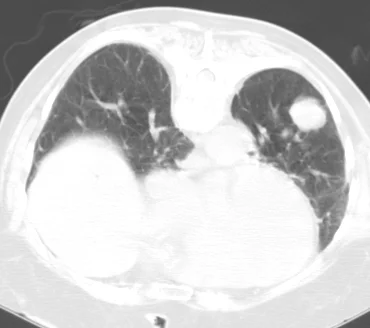

Interventional Oncology: Case 1

64 year old female with a history of smoking who presents with a new lung mass.